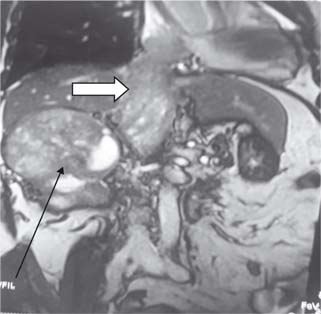

Figure 3: Level 4 thrombus with arrow (Black) showing mass in right kidney and white arrow thrombus in IVC extending to right atrium.

Figure 4: Opening of right atrium with arrow showing thrombus in situ.